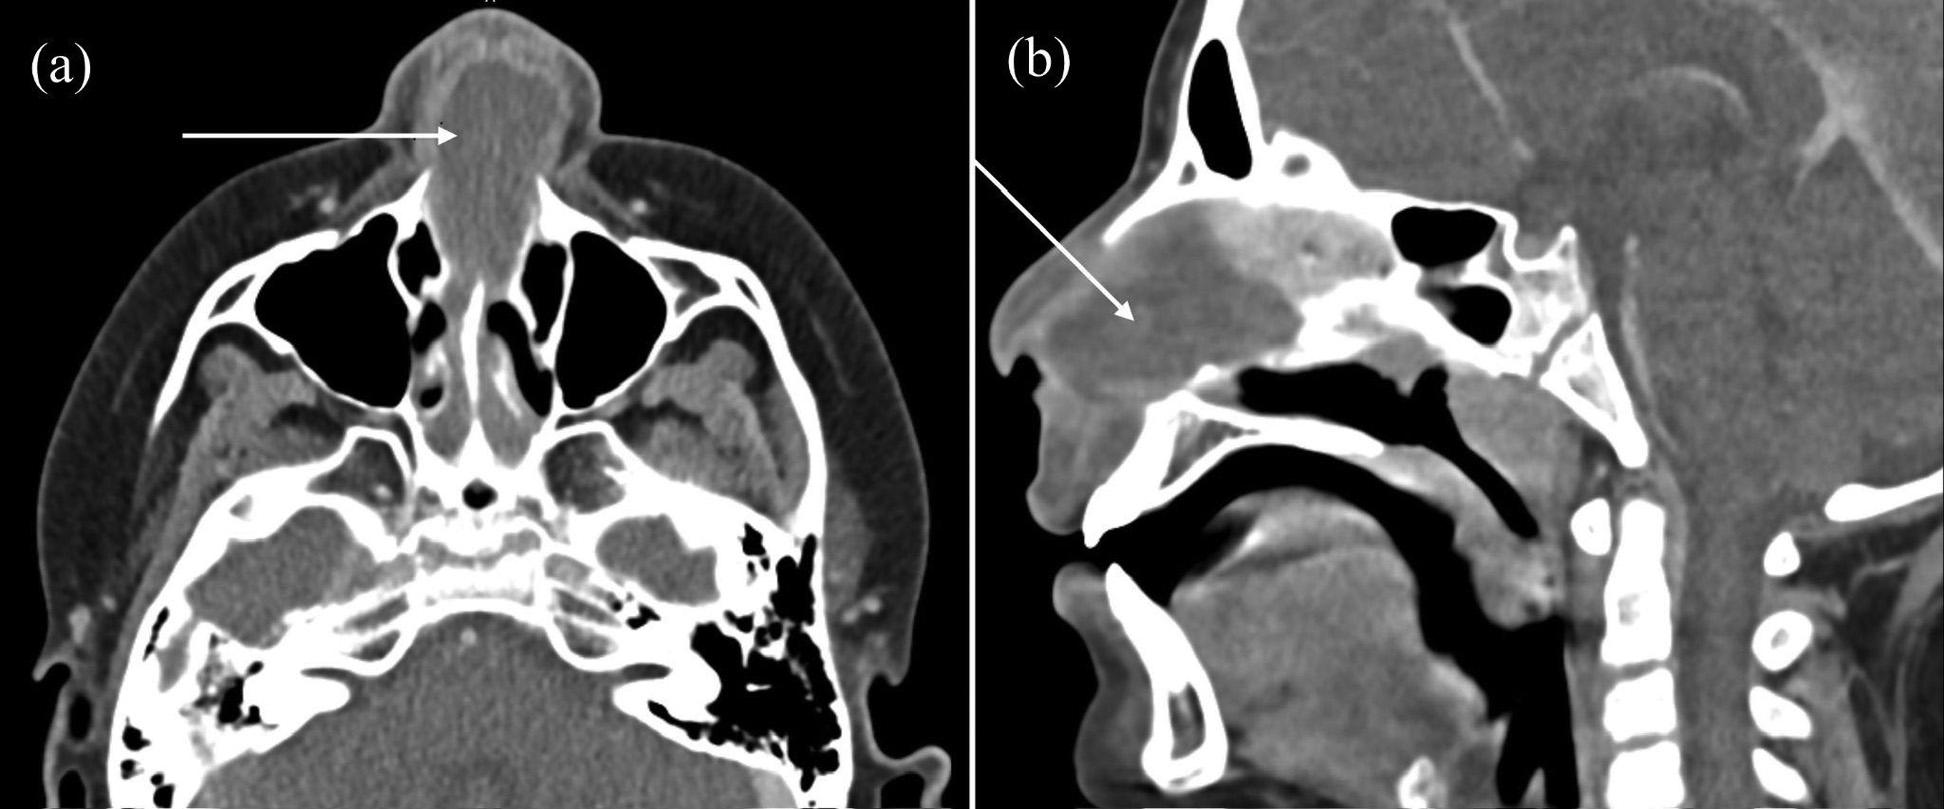

308 Painful Enlarging Cervical Mass in Young Male

Jacob Lawing, Jeremy Towns, Matthew A. Heimann

311 Atraumatic Infected Septal Hematoma in a Pediatric Patient

Osher Shefer, Jacqueline Le, Eshaan Daas, Eugene Hu